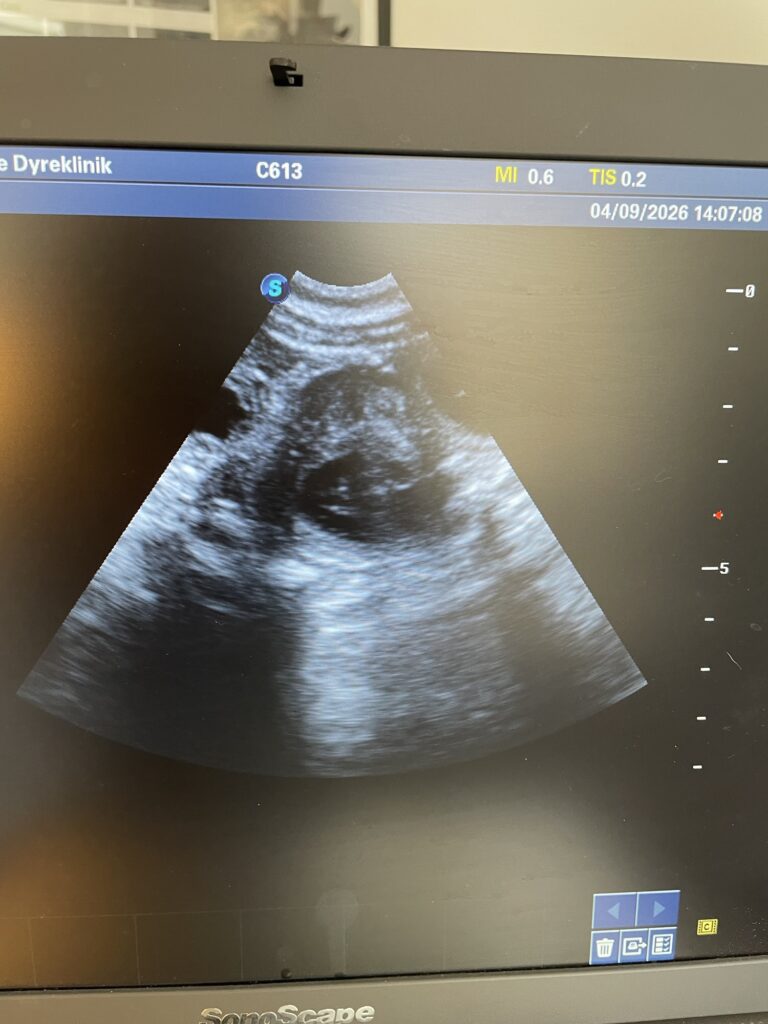

Karma venter hvalpe – et pænt stort kuld sagde dyrlægen – forventet ankomst ca. 15.maj❤️